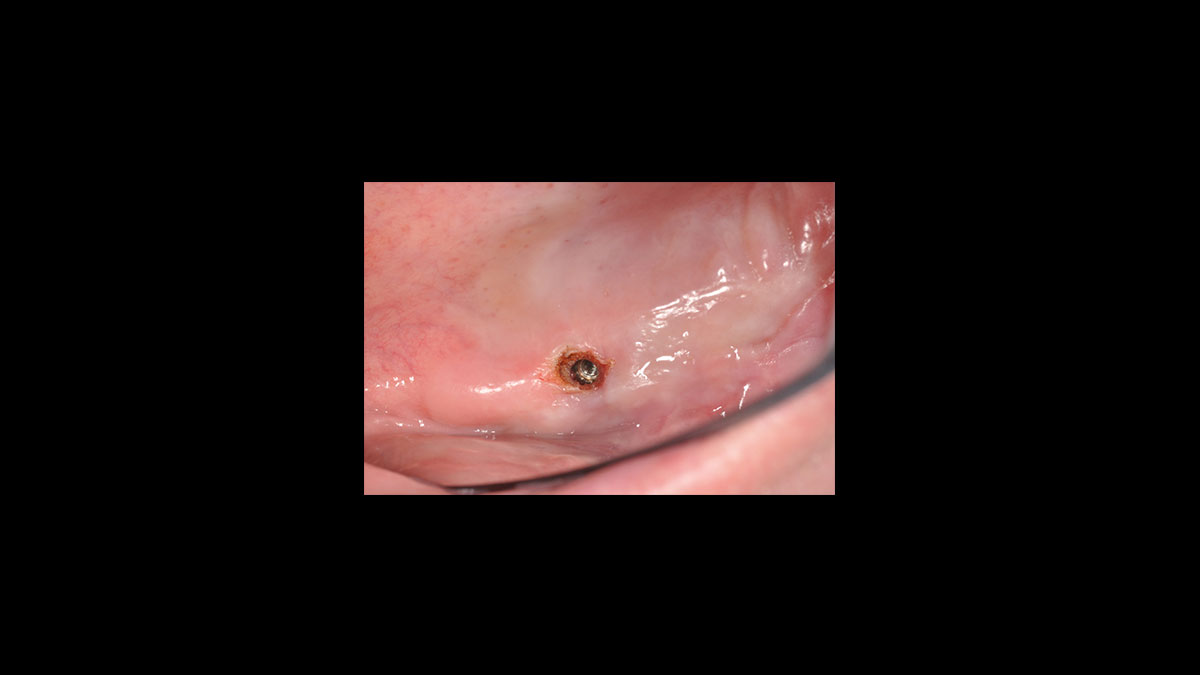

Implant uncovery